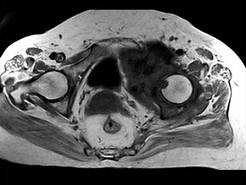

问题 患者 男,38岁,感觉左髋部疼痛,并逐渐加重,体检:左髋部明显肿胀压痛,无明显发热,请选择最佳诊断 ( )

选项 A、软骨肉瘤 B、软骨黏液纤维瘤 C、纤维肉瘤 D、骨肉瘤 E、骨巨细胞瘤

答案 A